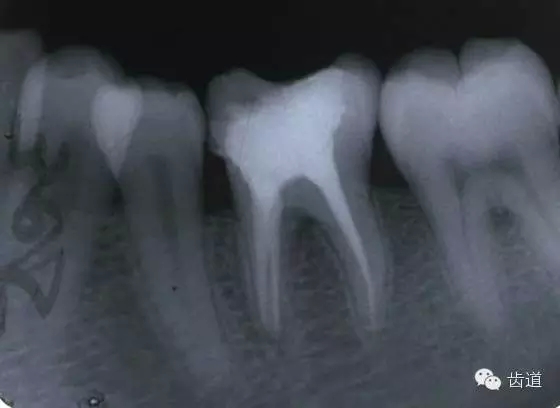

左上5牙頸部側(cè)穿

開(kāi)髓時(shí)鉆針進(jìn)入方向與根管走行方向不一致,鉆針需改變方向時(shí)。

牙長(zhǎng)軸傾斜,在傾斜方向的髓腔壁易穿孔

磨牙髓室頂、底距離接近時(shí),易將髓底穿孔。

左下6底穿

左上6底穿

根管壁穿孔多在根管彎曲處。

左上4鑄造樁側(cè)穿